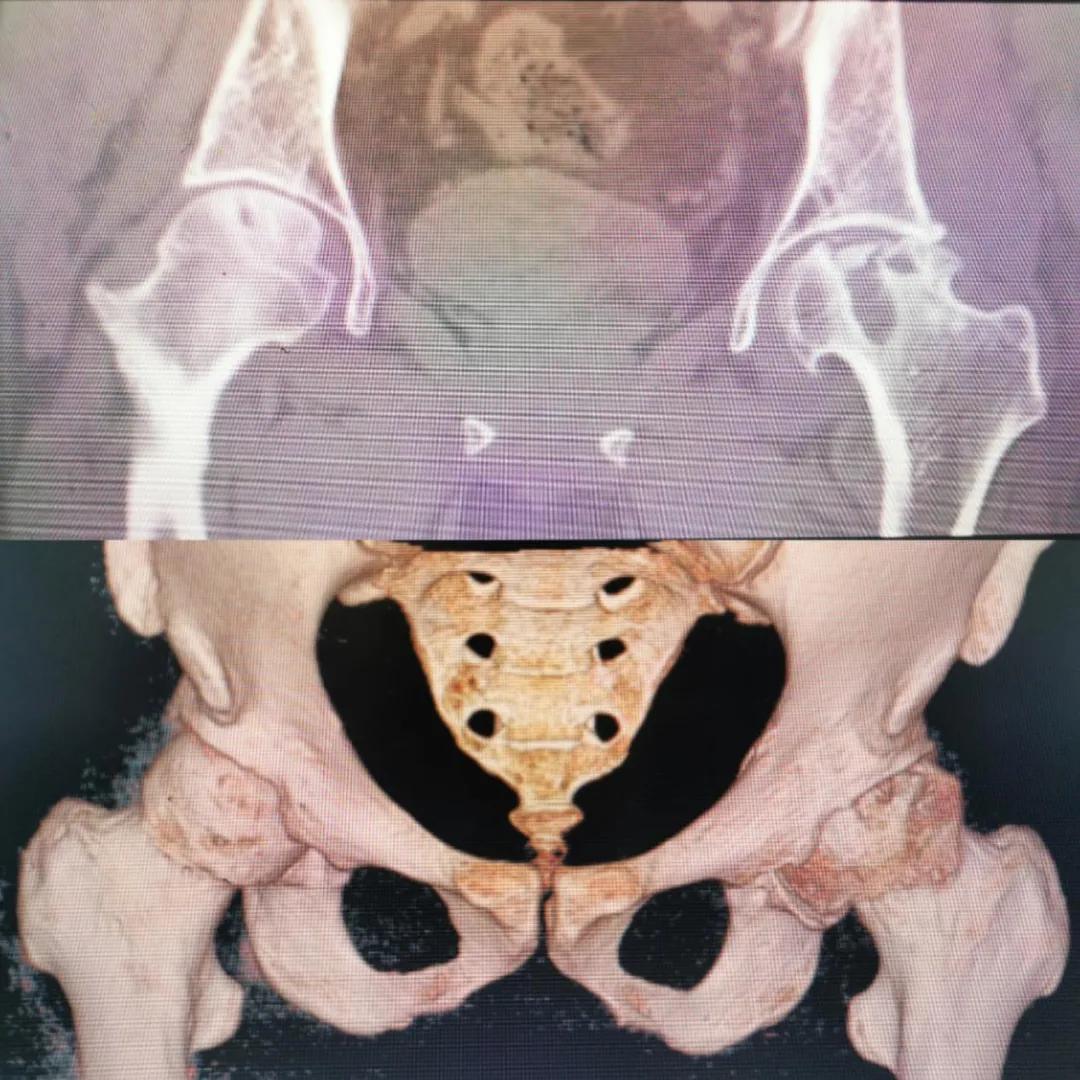

入院急查血結(jié)果提示炎癥反應(yīng),感染較重,凝血功能及肝功均不同程度損害;髖關(guān)節(jié)磁共振(MRI)檢查提示雙側(cè)股骨頭缺血壞死,繼發(fā)髖關(guān)節(jié)炎,左側(cè)髖周軟組織腫脹。醫(yī)療團(tuán)隊給出的初步診斷為膿毒血癥、股骨頭缺血性壞死、軟組織感染、皮膚潰瘍及閉孔神經(jīng)損傷。

圖片(圖為患者入院時髖部CT檢查)

追溯病史,患者訴前不久曾用蜂蜇療法治療股骨頭壞死,每日4次,每次100只蜜蜂蜇雙臀部、髖部,這才導(dǎo)致了病情急劇進(jìn)展。查明了來龍去脈,我院智能微創(chuàng)骨科醫(yī)護(hù)團(tuán)隊與患者家屬積極溝通病情,給予特殊級抗生素抗感染以及消腫、止痛等支持治療,同時對潰瘍創(chuàng)面進(jìn)行專業(yè)、規(guī)范的清創(chuàng)、換藥處理,保護(hù)創(chuàng)面降低感染程度;護(hù)理上輔助翻身,減少壓力性損傷。